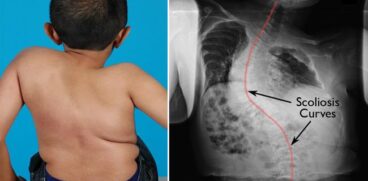

– o cocoașă grasă între umeri și gât

– probleme osoase